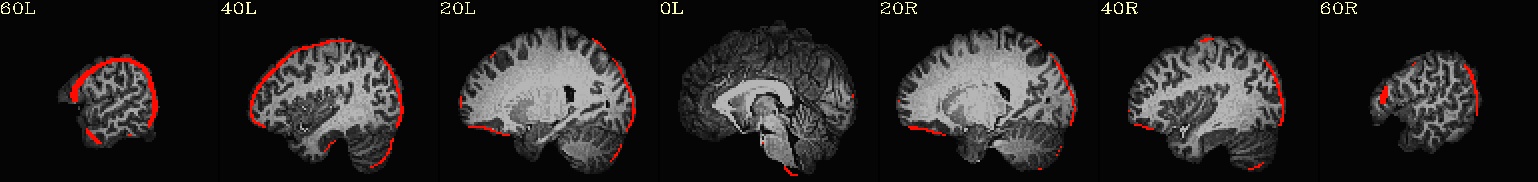

Running Preprocessing and First Level Analysis for sub-08#

All of the preprocessing steps (from setup through scaling) for subject sub-08 were introduced and explained in the example notebook about Preprocessing with AFNI- which is highly inspired by Andy’s Brain Book’s excellent AFNI tutorial. There, it is covered how to use afni_proc.py to generate an automated pipeline, and how to interpret each preprocessing block. In this section, we extend that workflow by adding a regress block to model task-related brain activity using a general linear model (GLM):

Preprocessing and GLM Workflow:

➡️ setup ➡️ tcat ➡️ align ➡️ tlrc ➡️ volreg ➡️ blur ➡️ mask ➡️ scale ➡️ regress 🧠

outputs: includes fitted time series, beta weights, and statistical maps from the GLM.

🧾 regress step: Incorporates timing files, HRF modeling (GAM), symbolic GLTs, and executes 3dREMLfit for improved autocorrelation modeling.